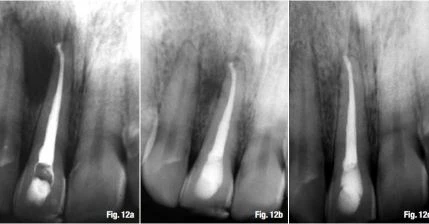

Một phương pháp khác, được ủng hộ bởi một nhóm các học giả nổi tiếng và các nhà lâm sàng giàu kinh nghiệm, tán thành rằng việc sửa soạn và trám bít trong những trường hợp như trên thì luôn chấm dứt tại lỗ chóp giải phẫu hay lỗ chóp trên X-quang, chóp răng trên X-quang. Hình 11a và b minh họa khả năng điều trị thành công càng lớn khi điểm kết thúc của tất cả các thao tác trong ống tủy nằm tại lỗ chóp giải phẫu, không phân biệt loại viêm quanh chóp. Nếu có thể, mục tiêu của điều trị triệt để là để tránh phẫu thuật quanh chóp (Hình 12a–c).

Quyết định chiều dài làm việc và cách xác định điểm chóp cuối cùng  tại điểm chóp phẫu thuật

Hình 12a–c: Trường hợp điểm kết thúc tại lỗ chóp giải phẫu hay chóp răng trên X-quang: Hình ảnh trước điều trị (a); sau 6 tháng (b); sau 2 năm (c).